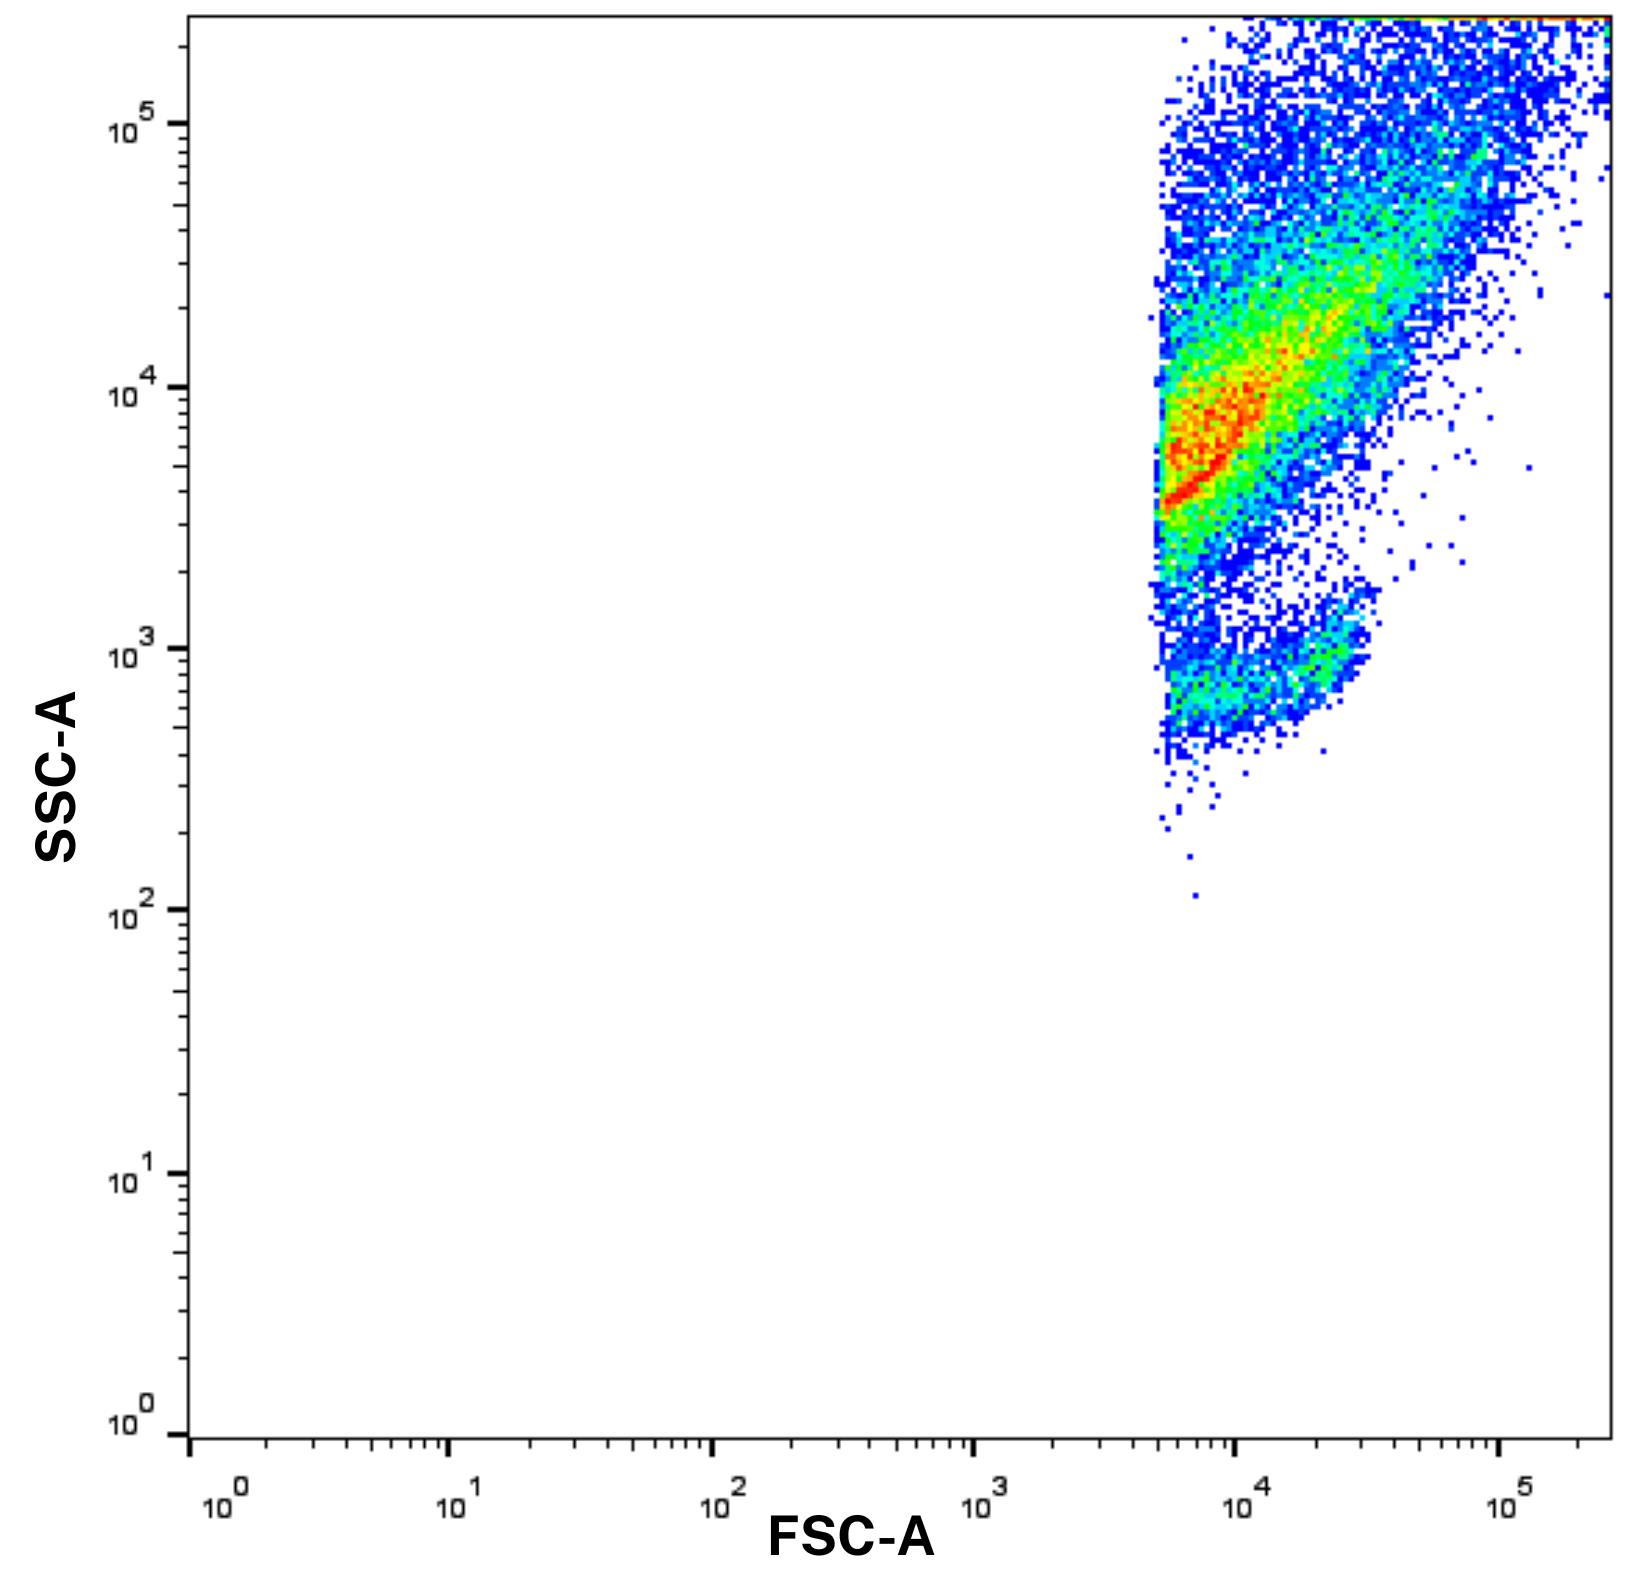

3. To ensure accurate detection of EVs, it is essential to optimize the forward scatter (FSC) and side scatter (SSC) settings of the flow cytometer. Standard flow cytometry settings are typically optimized for whole cells ranging from 5 to 10 μm in size. In contrast, EVs are considerably smaller (typically, 100–1,000 nm) and exhibit variable internal complexity, making them challenging to resolve with conventional FSC/SSC voltages.

4. Therefore, prior to sample acquisition, the flow cytometer should be set to high sensitivity mode. FSC and SSC voltages should be adjusted appropriately to reduce noise while still capturing small particles. Importantly, while cells are typically analyzed using linear FSC/SSC scales, switching to logarithmic scaling is essential for resolving the size differences present in EVs and other submicron particles. Calibration using size-standard beads (e.g., 100, 200, and 500 nm) is recommended to establish the detection range and gate the EV population accurately (Figure 2).

Figure 2. Forward scatter and side scatter (FSC/SSC) scale with logarithmic scaling before gating. Log scaling enhances the resolution of extracellular vesicles (EVs), which would otherwise be difficult to distinguish using standard linear settings.